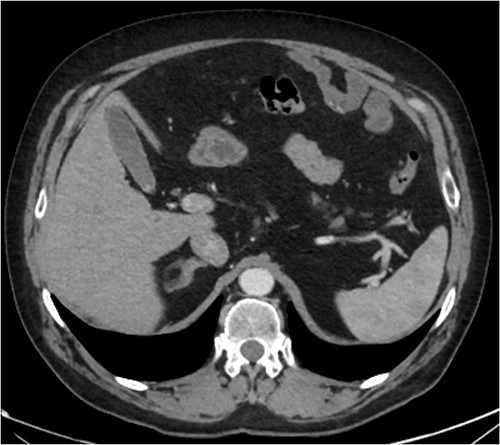

A CT abdomen-pelvis (CT-AP) revealed an acute haematoma inferolateral to the third part of the duodenum and another at the root of the mesentery. High density fluid related to the mesenteric bleed was also seen extending from the right para-colic gutter into the pelvis and in the peri-hepatic region. The patient was admitted under general surgery, stabilized with intra-venous fluid resuscitation, co-amoxiclav and metronidazole and cross matched for four units of blood. A CT-angiogram demonstrated acute haemorrhage throughout the abdomen with a 104 x 62 mm haematoma arising centrally at the level of L2 within the mesenteric fat (Fig. 1). The haematoma did not appear to originate from any specific mesenteric vessels but was related to some mid and distal jejunal loops. The angiogram also showed discontinuity when tracing the proximal and mid jejunal loops inferiorly, extensive haemorrhagic peritoneal fluid around the liver extending inferiorly (Fig. 2) and a small amount of peri-splenic haemorrhagic fluid. Curved reformatting of the angiogram revealed no abnormalities within the superior mesenteric artery (Fig. 3).

CT angiogram showing a large acute mesenteric haematoma. Figure 1 is taken from an axial section of the patient’s initial CT angiogram of the abdomen and pelvis. The arrow shown highlights an area of high-density fluid representing a 104 x 62 mm acute mesenteric haematoma.